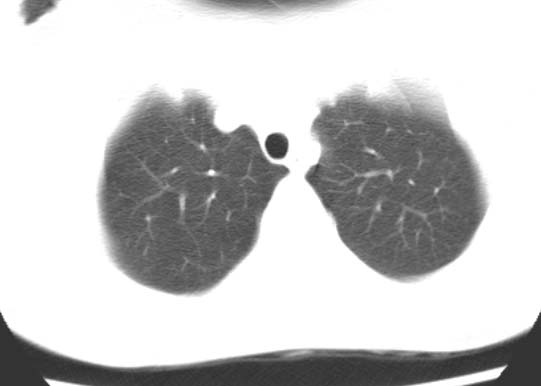

标题: CT25816:胸部CT,请会诊。

女 19岁,发热,咳嗽

考虑肺血管畸形可能性大,建议增强检查。或薄层ct后三维重建。

考虑右下肺动静脉畸形,建议增强进一步检查。

典型的支气管粘液栓,建议抗炎治疗复查,会有变化的。

考虑右肺下叶支气管扩张并黏液嵌塞。